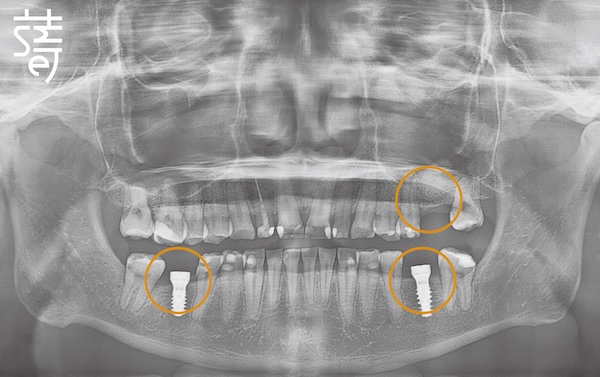

將牙齒重新排列整齊,調整上下咬合,把原本傾倒的第二大臼齒推回正確位置,為後續植牙和假牙重建打好基礎。

Teeth were realigned, the bite adjusted, and the previously tilted second molars repositioned, laying a solid foundation for implants and prosthetics.

第二階段:植牙重建缺牙區 Stage Two: Implants for Missing Molars

針對缺牙已久的後牙區進行植牙,恢復後牙支撐,避免整體咬合繼續崩塌,讓口腔受力更均衡。

Implants were placed in the long-missing molar areas to restore support, prevent further bite collapse, and balance oral forces.